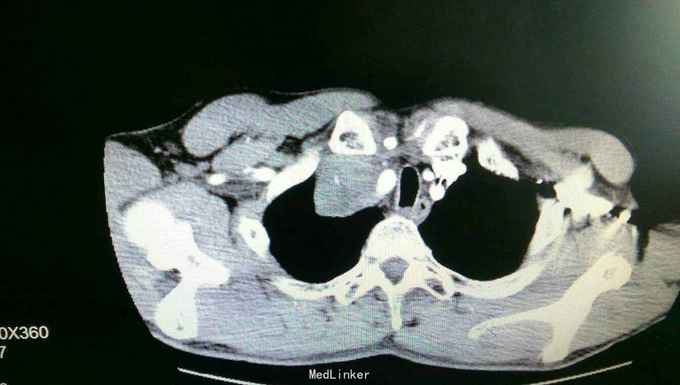

患者入院后,拟行左颌下肿块切除,在术前检查,术前准备时,常规胸片发现右侧肺部肿块,进一步行颈部及胸部ct检查,提示左颌下淋巴结肿大,转移性可能。右下肺周围性肺癌伴右肺门及纵膈多发淋巴转移考虑。决定先行左颌下肿块切除,明确诊断。术后病理示:左(左颌下腺)淋巴结转移性癌,来源首先考虑为肺。患者及家属考虑为晚期肿瘤,拒绝进一步手术治疗及化疗,下颌部切口愈合拆线后,出院。

患者出院后,门诊服中药治疗,定期复查。 讨论:患者因左颌下肿块前来就诊,术前检查发现肺部肿块,一元论考虑,应为肺部肿瘤转移所致。而且手术后病理亦证实。关键当下颌部出现肿块,应考虑肿块性质的鉴别。1.应考虑颌下肿块与颈部淋巴结的鉴别,尤其是无痛性肿块,要和淋巴结核及肿瘤等鉴别。2要和周围组织的肿瘤如甲状腺,鼻咽癌等浸润转移鉴别。3.要考虑纵膈,肺等远处转移。该患者为右下肺肿瘤已向纵膈及颈部,颌下转移,但患者临床表现仅有左颌下肿块,无胸闷气急,无咳嗽咳痰,虽ct检查发现纵膈及颈部多发淋巴结肿大,患者却无上腔静脉回流受阻,颈部浅表淋巴结未能扪及。该病例提示我们,当患者颈部出现肿块,应仔细检查,多些鉴别,以免漏诊。